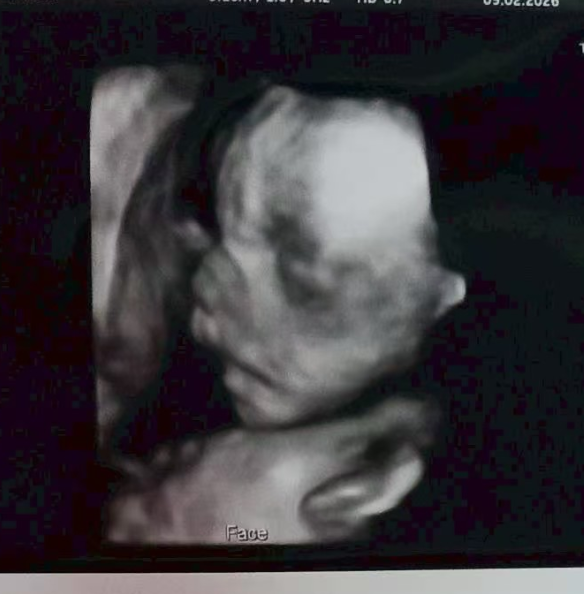

2月14日,孕24週,四維大排畸順利通關!

喜報!1月28日四維檢查順利通關。胎兒發育無異常,恭喜喜獲健康男寶,圓滿達成心願

1月15日完成四維排畸檢查,

結果顯示未見異常,各項發育指標正常。